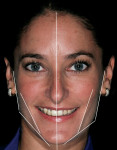

The first instinct of practicing clinicians is to see the smile. The first exercise in these types of cases is to back up and see the progression of development that has occurred. The idea is to find the frame within which the smile belongs, then focus on parameters of smile design, and finalize by looking at individual tooth form.3 The parameters guiding the facial analysis are the horizontal plane, vertical plane, the relation of thirds of the face, and the strong side versus the weak side (Figure 1). These elements provide the frontal framework of the smile. In essence, the clinician should be able to visualize the proper incisal plane that the gingival plane should be paralleled to, the axial inclinations, the position of the teeth in the lower third of the face, and the angulation of the buccal corridor. Upper lip support, lower lip relation, and the occlusal plane all influence sagittal reference, and two characteristics of the smile that are best visualized in the sagittal dimension are overjet and incisor angulation. Finally, the clinician should focus on the oblique plane, which provides reference to the smile arc and orientation of the palatal plane.4 Diagnostically, the practitioner should consider the three-dimensional position of the smile, then use a knowledge of smile design and tooth proportion to finish creating natural esthetics.

Clinicians should orient themselves with a vertical and horizontal plane of reference. Those who have painted, sculpted, or sketched are aware of the need for perspective in space. This is referred to as the “Facial T” (Figure 2). Attractiveness results from a general sense of parallelism and symmetry between structural facial features, because parallelism is the most harmonious relationship between two lines.5 The interpupillary line represents the horizontal perspective that guides evaluation of the incisal plane, gingival margins, and the position of the maxilla (Figure 3, Figure 4, Figure 5). It should be noted that the interpupillary line is not always the only reference that can be used, because there are situations in which patients may have an asymmetrical position of the eyes. In this case, a second reference, which is perpendicular to the facial midline, can be used.6 The vertical element is the facial midline bisecting the center of the face and extending through the bridge (nasion) of the nose and philtrum. This midline becomes reinforced by the direction and axis of the dental midline. If the dental midline cannot be coincident with the facial midline, it is best to anchor the smile by creating the midline vertical. Severe discrepancies may indicate orthodontic movement (up to 2 mm off the facial midline).7,8 The facial midline aids in evaluating the location and axis of the dental midline along with mediolateral discrepancies in tooth position.

Next, the clinician should consider the growth and development of the patient to determine how to treat the anterior esthetics. The upper third of the face is the area bordered by the base of the hairline—or beginning of wrinkling of the forehead—to the top of the brow. The top of the brow to the base of the nose is the middle third, and the base of the nose to the base of the chin is considered the lower third. This evaluation will reveal any abnormalities in anterior facial height (Figure 6). As ramus length varies, both anterior facial height and tooth display vary. Not only can this determine the need for periodontal surgery or orthodontic movement, it also defines the buccal parameters of the buccal corridor. A short ramus with normal posterior eruption results in an obtuse gonial angle, or the “long, narrow face.” The patient may develop either an anterior open bite, which would indicate a combination of orthodontics and or prosthetics, or excessive gingival display, which would indicate maxillofacial surgery or hard-tissue crown lengthening and prosthetics. Conversely, decreased anterior facial height is due to a long ramus, an acute gonial angle, and results in inadequate maxillary tooth display and a “square face.” This can be treated orthodontically or restoratively. Again, these are generalizations, and each case has its own set of parameters. What is important to remember is that people’s faces are not symmetrical from right to left. The gonial angles are influenced by the strength of the masseter muscle—the stronger the masseter muscle (strong side), the more acute the gonial angle. From a frontal view, this creates an angle that should parallel the canine, premolars, and molars—which comprise the buccal corridor. Starting from the condyle to the pogonion, the canine and buccal corridor should parallel this angle in order for the teeth to “frame” the face. If the incisal tips of the canines or premolars are hanging over the lower lip, it means the teeth have been built out too far buccally; conversely, if there is too much negative space, the smile has not been built out enough. An important point, however, is to understand what building the smile out does to a patient’s face: It essentially widens, or gives horizontal prospective to, the lower third of the face. Women who have lost sufficient cheek fat can have a “smile lift,” which, in essence, gives the illusion of fuller cheeks. Understanding what the buccal corridor does is very powerful in creating the desired look.